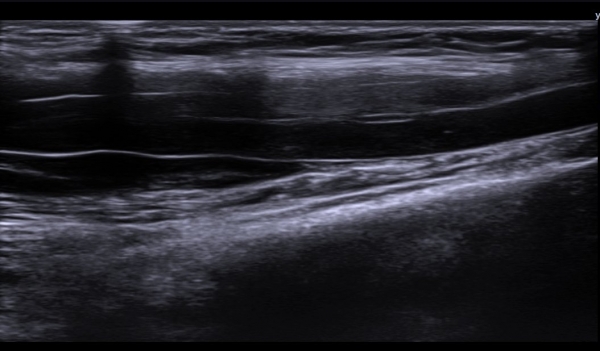

ÃÊÀ½ÆÄ  °Ë»ç  : À­ÆÈ ±ÙÀ§ºÎ Á¤Áß ½Å°æ Ⱦ´Ü¸é°Ë»ç¿¡¼­ Á¤Áß ½Å°æÀÇ ºÎÁ¾°ú ÀϺΠ½Å°æ¼¶À¯ÀÇ Àú¿¡ÄÚ ºÎÁ¾ÀÌ °üÂûµÈ´Ù

(»çÁø 1, 2). ŽÃËÀÚ¸¦ Á¶±Ù ´õ ±ÙÀ§ºÎ·Î À̵¿ÇÏ´Ï Á¤Á߽ŰæÀÇ Àú¿¡ÄÚ ºÎÁ¾ÀÌ °üÂûµÈ´Ù(»çÁø 3, 4).